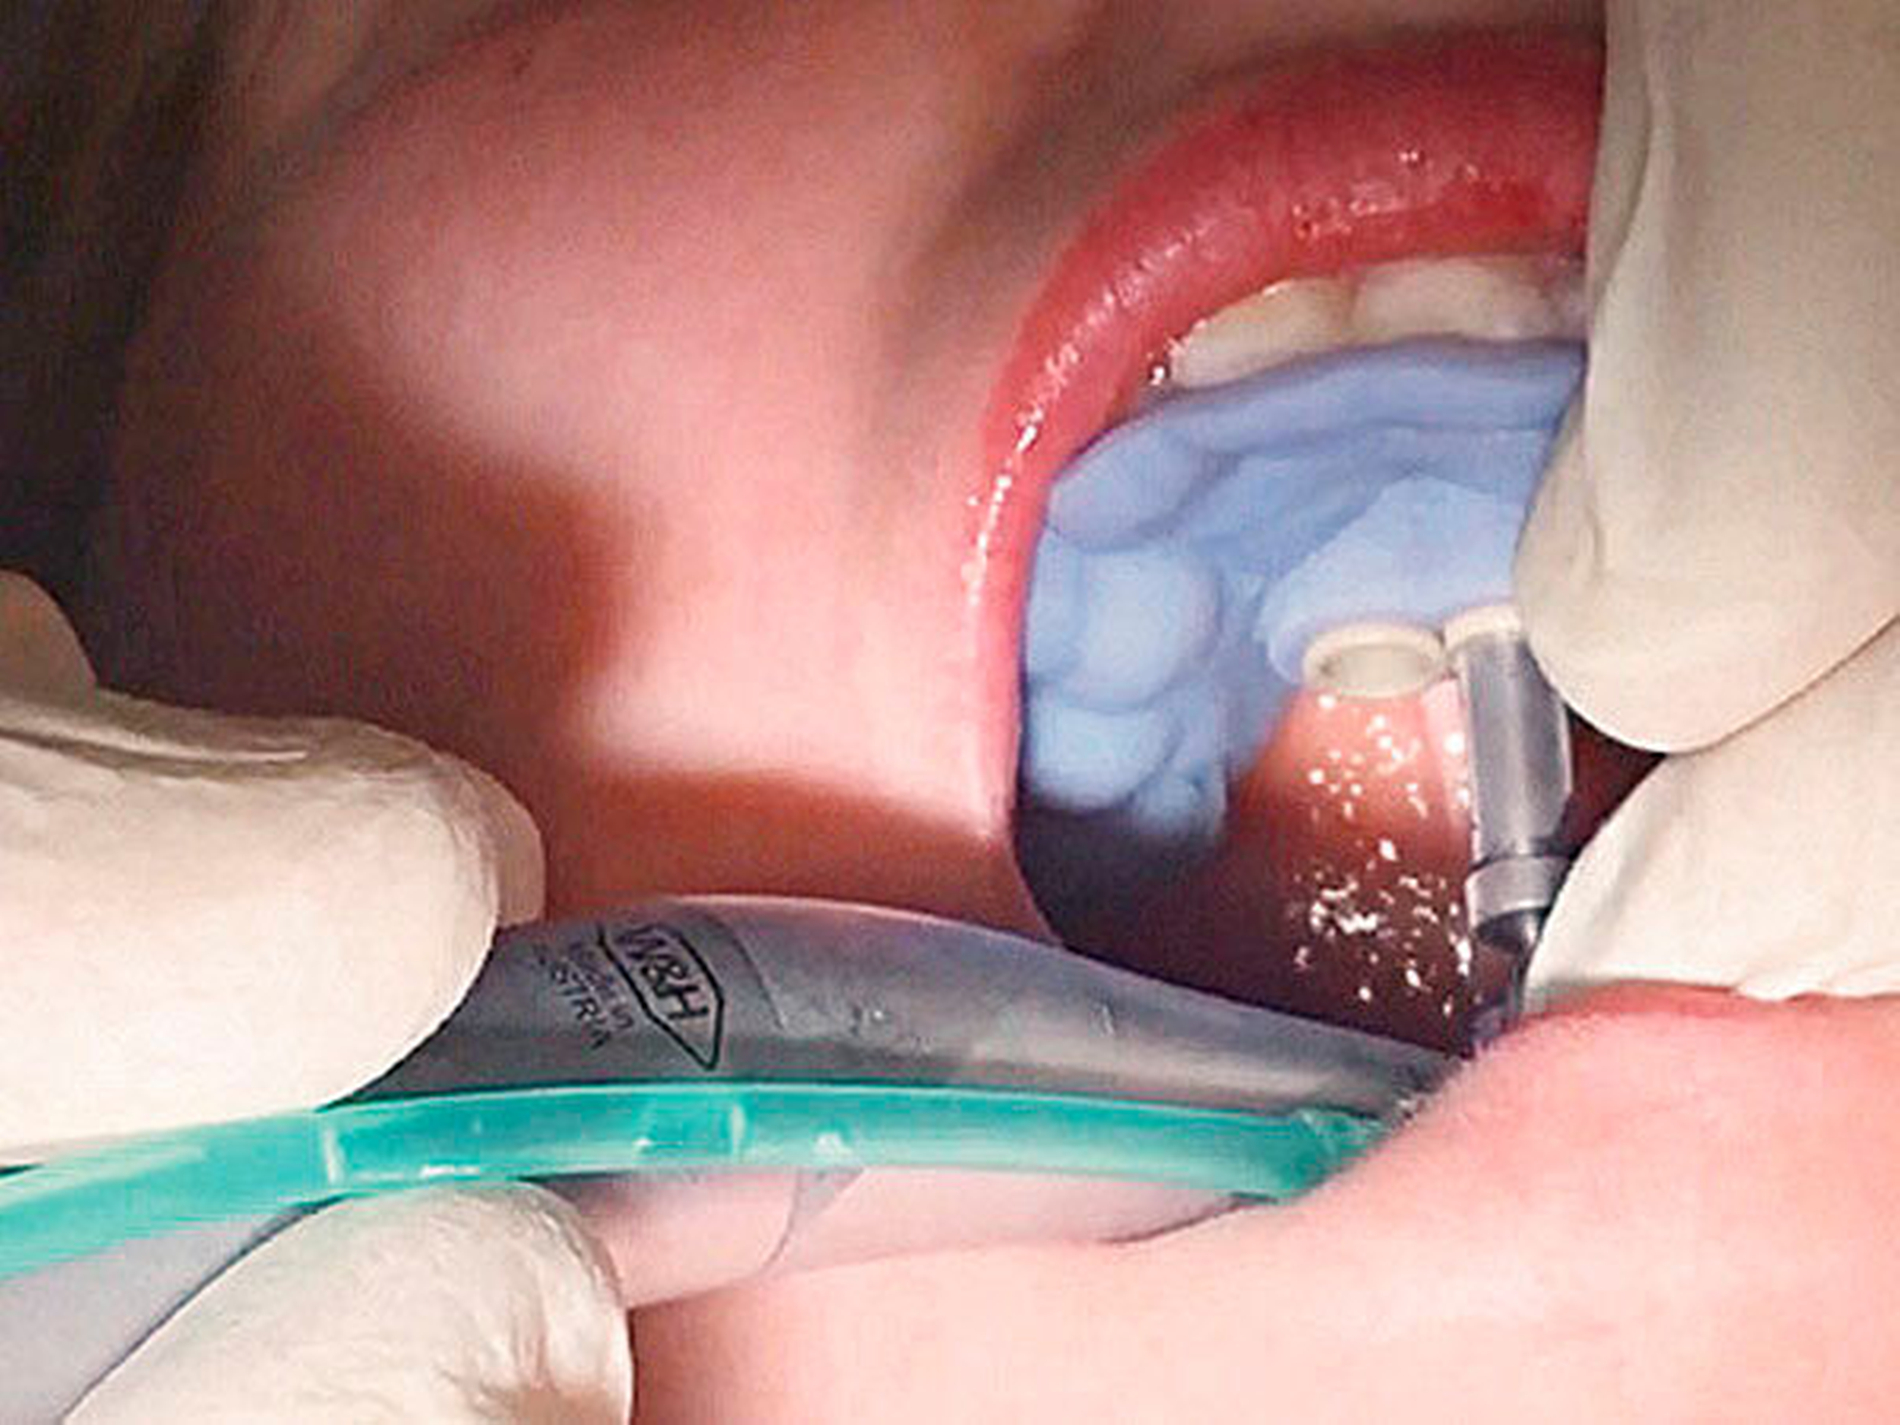

Das Prinzip einer CAD/CAM-gesteuerten Insertion wird anhand einer zehnjährigen Patientin mit einem Platzmangel für die oberen Eckzähne dargestellt (Abbildungen 4a, 4b). Die Behandlung begann mit dem Anpassen von Molarenbändern und einem Silikon-Abdruck des Oberkiefers, der mit dem FRS an das zahntechnische Labor gesendet wurde und dort mit dem FRS der Patientin überlagert wurde. So konnten geeignete Insertionsstellen virtuell geplant werden (Abbildungen 1, 2a, 2b). Nach Rücksprache mit dem Behandler bezüglich der Mini-Implantatpositionen erfolgte die Herstellung der Insertionsschablone (Abbildung 3). Parallel dazu wurde auch der Beneslider [Wilmes, 2010] hergestellt, der zusammen mit der Insertionsschablone geliefert wurde (Abbildung 5). Mithilfe der Insertionsschablone konnten die Mini-Implantate und der Beneslider im selben Termin eingesetzt werden (Abbildungen 6, 7a, 7b). Nach 10 Monaten Distalisierung waren die Molaren in der Zielposition und es war ausreichend Platz für die Eckzähne vorhanden (Abbildungen 8a, 8b), so dass Brackets für die zweite Phase der Behandlung eingesetzt werden konnten. Die Multibracket-Apparatur (Abbildung 9) konnte nach 12 Monaten entfernt werden (Abbildungen 10, 11).